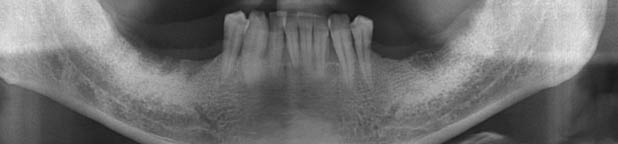

인터넷에서 찾은 현재 나의 상태와 가장 동일한 X-Ray 사진

제작년 병원에 갔을때는 의사 왈 " 허 거~ 젊은 사람이 이빨 상태가 80대군요. 조금만 늦었으면 틀니를 할뻔 했어요~~" 이랬습니다.

이번에 처음 찾아갔던 치과는, 잇몸의 골 유실이 심해 임플란트도 불가하고, 틀니를 해야할것 같다고 하더군요.

그래서 찾아간 다른 병원은 충분히 임플란트가 가능하다고 합니다.

X-Ray 및 CT 촬영까지 마친후, 발치한 병원에서 그 자리에서 양쪽에 각 1개씩 총 2개의 어금니를 임플란트 시술하기로 결정했습니다.